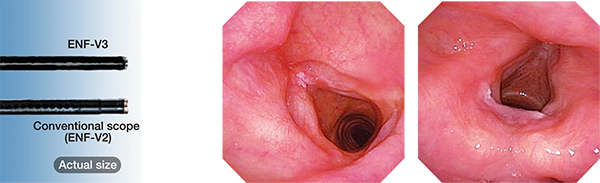

Surprisingly Slim Diameter

The distal end of the ENF-V3 scope is only 2.6 mm in diameter, Also, the differencebetween diameters of the distal end and the insertion tube is minimal, This makesinsertion into tight nasal passages much easier. And with the CCD chip's improvement.even this slim scope delivers exceptional image quality.

OLYMPUS leads the world in endoscopes. We always listen carefully to physiciansand specialists on the medical front lines. Over and over, they have made twocomments that particularly resonated with us, “We want to make every diagnosismore accurate." and "We want smoother treatments for our patients." We drew uponour decades of endoscope expertise and combined it with OLYMPUS' proprietaryoptics technology. Now we can offer two new solutions: ENF-VH, with HD highdefinition, and ENF-V3, which maintains high image quality while reducing the distaend outer diameter to a mere 2.6 mm. With these two new products, OLYMPUS offersa new examination environment for rhino-laryngo videoscopes.

ENF-V3, crisp, high-resolution images with adistal end diameter of only 2.6 mm

- Distal end outer diameter 2.6 mm

- High image quality